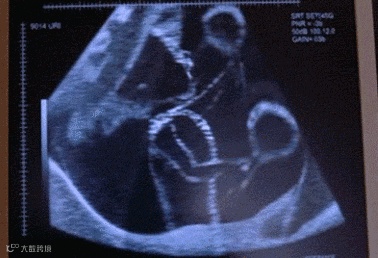

[超声检查]

彩超能够快速确定脐带所在的位置,直观显示出血流的流向和缠绕的周数,能够迅速准确地检查出胎儿是否发生了脐带绕颈。普通的B超准确性略差。

不得不提的是,当孕妇采取B超检查胎儿是否脐带绕颈的时候,一定要注意是不是假性的。

所谓假性脐带绕颈就是脐带并没有缠绕住胎儿的颈部,只是挡在了胎儿的颈部,通过B超影像,会错误地认为脐带绕颈了。

胎儿颈部有“V”形压迹,表示脐带绕颈一周;

“W”形,表示脐带绕颈2周;

“波浪”形表示脐带绕颈两周以上。